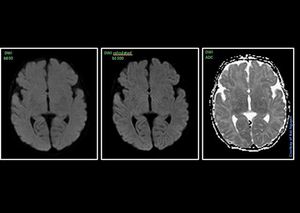

MRI Neuro Imaging – feed & wrap neonatal @ Siemens 1.5T AvantoFit Utilising the Pediatic 16ch coil in the combination with quiet sequences give results. I’m just surprised a feed & wrap baby can lie so still during a DWI sequences. Quiet DWI is not 100% quiet, but of course less noise compared to a standard DWI. This sequences is available on E11C software – qDWI.#s_mri #siemens #mri #quiet_suite